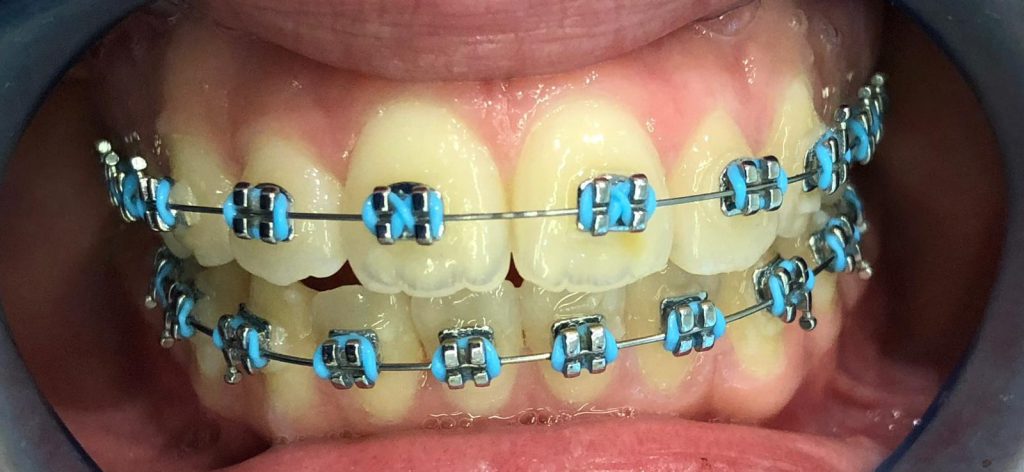

זהו מדע בתחום רפואת השיניים שמטרתו לתקן את הכלים ויישור השיניים, לתקן את היחס של הלסתות לפנים ולתקן צפיפות, עיוות או רווחים בשיניים. צורות יישור שיניים: 1- פלטות מתכת 2- פלטות קרמיות 2- פלטות שקופות 4- פלטות ניידות סוג הפלטה המתאימה למקרה נקבע לאחר האבחון הראשוני.